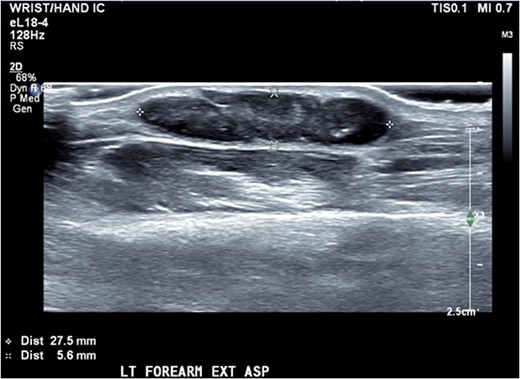

Ultrasound of the forearm revealed a 2.8 × 2.3 × 6 mm hypoechoic fusiform mass within the subcutaneous adipose tissue (Fig. 2). It was well marginated with relatively minor internal vascularity and with no extension into the deep soft tissue planes.